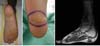

Menino admitido aos cinco anos de idade no Serviço de Ortopedia do Hospital Sarah apresentando história de surgimento, aos seis meses de vida, de tumoração na região plantar direita, indolor, de aspecto vinhoso e sem sinais inflamatórios. Submeteu-se a dois procedimentos cirúrgicos para exérese em outro serviço médico, aos dois anos de idade, com recidiva após três meses, e aos quatro anos, com recidiva a seguir, tendo recebido o diagnóstico de fibromatose plantar. Quando foi admitido neste hospital apresentava recidiva tumoral na região plantar e dificuldade para realizar o apoio plantar à direita, devido à dor local, e para o uso de calçados. No exame físico apresentava tumoração endurecida de aspecto cicatricial, não dolorosa à palpação, com extensão de mais ou menos cinco cm no seu maior diâmetro, localizada na região plantar direita (Figura 1). Realizou-se radiografia plantar em AP e perfil, e ressonância magnética nuclear que mostraram lesão na região plantar posterior medindo no sentido látero- lateral, 3cm de comprimento x 2cm de espessura, respeitando a fáscia plantar e direcionada à pele. Apresentava hemograma, contagem de plaquetas e coagulograma normais, não se evidenciando fenômeno de Kasabach-Merritt. Indicou-se biópsia, cujo laudo evidenciou hemangioendotelioma cutâneo kaposiforme. Realizou-se a exérese tumoral marginal mantendo a fáscia e sutura primária de lesão medindo 3x2cm; apresentou recidiva após seis meses de pós-operatório. Optou-se por ampliar a margem cirúrgica lateral e em profundidade em 2cm, realizou-se a ressecção elíptica incluindo pele, subcutâneo, fáscia muscular até o calcâneo, medindo 5x3x2cm.

O exame de congelação transoperatória mostrou tecido fibrótico, porém sem evidência de tumor na margem profunda, sendo feita a exérese da fáscia plantar, do periósteo do calcâneo e realizada a reconstrução com rotação de retalho do cavo plantar de pedículo medial medindo 6x4cm e enxertia de pele parcial na região doadora no médio-pé, sutura com monocryl 4-0 e curativo de Brown na área enxertada. O enxerto foi retirado com faca de Blair da porção medial da coxa homolateral; o curativo foi mantido por uma semana, quando se observou integração total do enxerto de pele. Orientou-se repouso com o membro elevado sem carga até a integração completa do retalho e enxerto de pele, por 2 semanas; observou-se evolução satisfatória do retalho com remissão do quadro de dor, sem recidiva tumoral no seguimento de 15 anos (Figura 2).